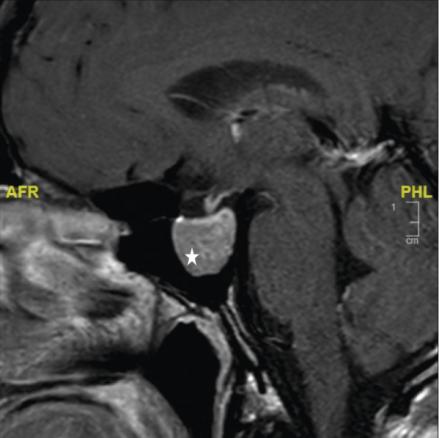

La réalisation d’une IRM hypophysaire permet de visualiser la tumeur (fig. 3, 4 et 5), d’évaluer sa taille et son éventuelle extension aux structures adjacentes.